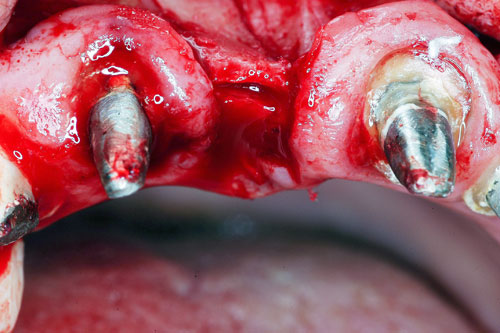

Mientras dichos movimientos ortopédicos se producen (período que supondrá otros seis meses), estudiamos los actos quirúrgicos a realizar en los cuatro implantes que pondremos. De acuerdo al estudio Desatascan realizado observamos tres situaciones diferentes: 1º-El Primer Molar Inferior Izquierdo, lo instalamos mediante Cirugía Minimamente Invasiva , con la aplicación de una Férula Quirúrgica Obtenida de los datos del scanner tratados con un programa de CMI (Cirugía Minimamente Invasiva), previa prueba en un modelo estereolitográfico, ya que la altura ósea era apenas de 9 mm. 2º- El Primer Molar Superior Derecho, se implantará mediante una ligera Elevación Atraumática (Trans alveolar) de Seno una vez logrado el espacio mesio distal necesario. 3º- El Incisivo Central Superior Derecho ausente, cuenta con un sustrato óseo prácticamente inexistente. El espesor de la tabla era de menos de 2 mm. Los caminos posibles a seguir para contar con una Rehabilitación de piezas independientes son dos: Optamos por esta segunda opción por ser menos cruenta y no necesitar de una zona dadora. Técnica esta que pondremos en práctica en dos etapas diferidas: 1º-Incisión horizontal palatinizada, incisiones peri rodetes gingivales e incisiones de descarga. Dilatación que comenzamos con dos incisiones de descarga sobre la cortical vestibular realizadas con disco. y el comienzo de la dilatación propiamente dicha mediante una hoja de bisturí, para luego seguir con un periostótomo . Recién después de alcanzada una cierta separación de la cortical vestibular de la palatina, empezamos con los dilatadores roscados. En este punto podríamos haber utilizado sin riesgos un Implante de 3,8 mm de diámetro, pero a fin de mejorar la estética del pilar emergente decidimos rellenar con material osteoconductor y osteoinductor (BiOss) y cubrir mediante membrana reabsorvible ( Bio Guide). 2º-Implantación seis meses después. Mientras se van cumpliendo los tiempos antes mencionados, y comprobamos reiteradamente la funcionalidad de la oclusión con los provisorios, tomamos impresiones definitivas y construimos primero el maxilar inferior, para definir en primer término la porción inferior de la Guía Anterior., y a nivel posterior Curvas y Microplanos. Para luego realizar los cuadrantes premolar- molar del superior: La espera de la regeneración ósea y sus tiempos pertinentes, más la espera de los tiempos de la implantación, nos obligaron a modificar las etapas del protocolo D.AT.O de manera de mantener la –D- mediante el sector superior de la GA. en provisorios, mientras fuimos resolviendo en forma definitiva los demás sectores. Ya pasados los meses necesarios para recrear un hueso adecuado en el área del Incisivo Superior Derecho, procedemos a resolver la implantación de dicha zona, observando que todo el esfuerzo dedicado al mismo había sido inútil, ya que la formación de hueso se produjo minimamente. Cuatro meses después tomamos impresiones del sector Antero Superior de la Guía Anterior, incluyendo el arrastre de un transfer . Seguimos modelando la encía con un nuevo juego de provisorios. Y se construye entonces el sector superior de la Guía Anterior. Se efectúa un control radiográfico a los 6 meses. Se ha intentado mostrar en esta Rehabilitación, que a pesar de las distintas circunstancias de cada paciente, siempre debemos tener en cuenta la necesidad de ejercer la DESOCLUSIÓN del caso como prioridad número uno, para luego perseguir la ALINEACIÓN TRIDIMENSIONAL de las arcadas y obtener así una OCLUSIÓN equilibrada. D.AT.O. ES EL PROTOCOLO QUE DEBEMOS SEGUIR EN TODA REHABILITACIÓN. BIBLIOGRAFÍA 1)William Mc Horris,B.S.,D.D.S. Oclusión. Con especial énfasis sobre :El rol funcional y parafuncional de los dientes anteriores. 2)Von Spee , Craff(Anatomista alemán, describió la curva de compensación de la articulación de molares y premolares).CURVA DE SPEE 1.89 3)Stuart,D.”Some aspects of the inervation teeth.”Procedings of Royal Society of Medicine.20:1675,19274)Muhleman,H. y Savdir,S”Tooth movility-its causes and significance”Journal of Periodontology ,36:153,Marzo ,Abril,1965. 4)Muhleman,H. Y Savdir,S”Toothmovility its causes and significance” Journal of Periodontology,36:153,marzo,abril,1965. 5-Oclusión y Diagnóstico en Rehabilitación Oral. 6-Anatomia Odontológica. 7-A contribution to the study of the movementes of the mandible. 8-Celenza F.W, Nadeskin J.F.,Oclusión.Situación actual. 9-D´Amico 10-Dawson P.E. 11-Huffman –Regenos. 12-Hobo S.-Takayama H.A. 13-Lucia V.O 14-Mc Horris. 15-Mc Horris. 16-Stuart C. 17-Vartan Veshnilian 18-Alvarez Cantoni H. AUTOR:Ratificación del Protocolo en Rehabilitación Bucal a pesar de las incidencias propias de cada caso clínico. A propósito de un caso.

Verificamos también el escaso ancho crestal, lo que nos obliga a utilizar dilatadores roscados y un osteótomo para elevar inicialmente la membrana de Schneider.

B-Dilatación Crestal mediante Dilatadores Roscados previa Corticotomía Vertical.

Esperamos seis meses antes de implantar.

No obstante pudimos implantar satisfactoriamente mediante un implante de 4.2 mm. de ancho y 14 mm. de largo, con una nueva R.O.G.